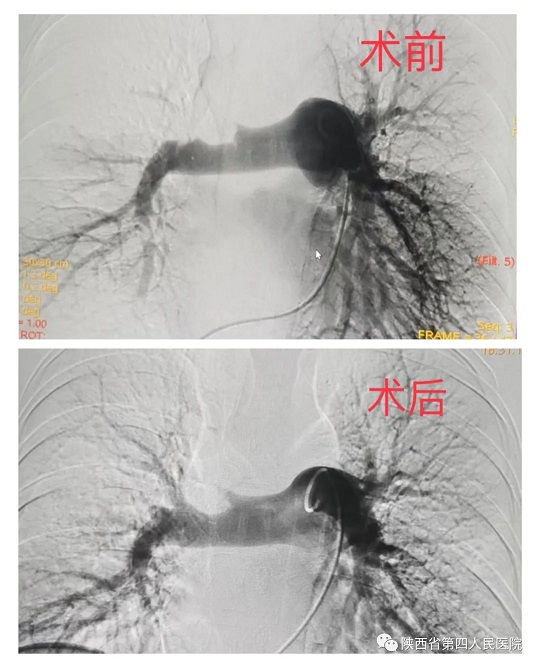

近日,亚色视频 心血管内科专家团队成功救治了一名突发急性肺栓塞的患者。经充分评估病情后,为患者行急诊手术,通过医护人员准确、及时的救治后,患者转危为安。患者,年轻女性,37岁,因外伤骨折术后卧床40余天,活动后出现胸闷、胸痛、气短,及一过性意识障碍,家……